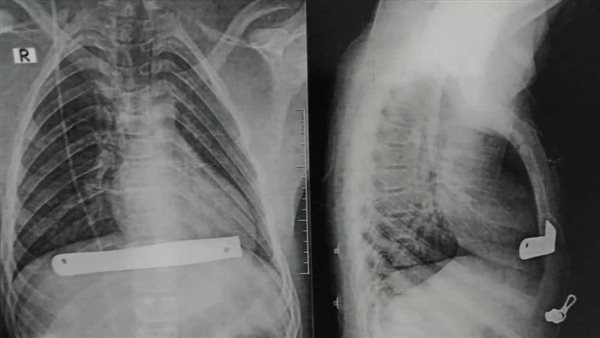

واستطاع الفريق الطبي إصلاح التحدب واستئصال جزء من عظمة القص وغضاريف الضلوع الأمامية وتركيب بار معدني مؤقت لإعادة تنظيم عظمة القص ليكون نمو غضاريف الضلوع الجديدة في مستوى واحد.

وأضاف أنه تم خلال الجراحة تركيب بار معدني مؤقت لإعادة تنظيم عظمة القص ليكون نمو غضاريف الضلوع الجديدة في مستوى واحد بعد ذلك، وتمت الجراحة بجرح تجميلي بسيط 5 سم فقط، وحاليا خرج المريض بنجاح ويتماثل للشفاء الآن بالعناية المركزة الخاصة بالقسم.